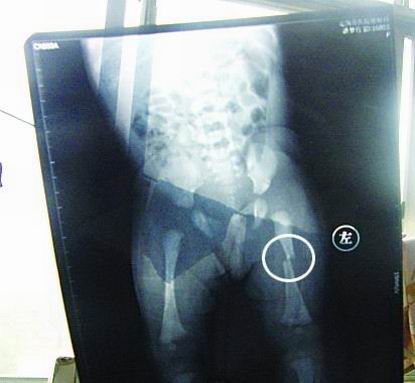

CT顯示小夢(mèng)竹左下肢骨折

今年7月2日下午,定陶縣南王店鄉(xiāng)沈莊村孕婦聶元真,在定陶縣人民醫(yī)院剖腹產(chǎn)下一女?huà)耄∶麨榕藟?mèng)竹。醫(yī)院說(shuō),嬰兒出生后窒息,診斷為新生兒缺血缺氧性腦病,頭皮血腫。當(dāng)晚發(fā)現(xiàn)女?huà)胱笙轮课划惓,第二天拍片顯示為左下肢骨干骨折。7月3日,潘夢(mèng)竹的頭顱CT顯示其頭頂部骨折,蛛網(wǎng)膜下腔出血,顱內(nèi)血腫。